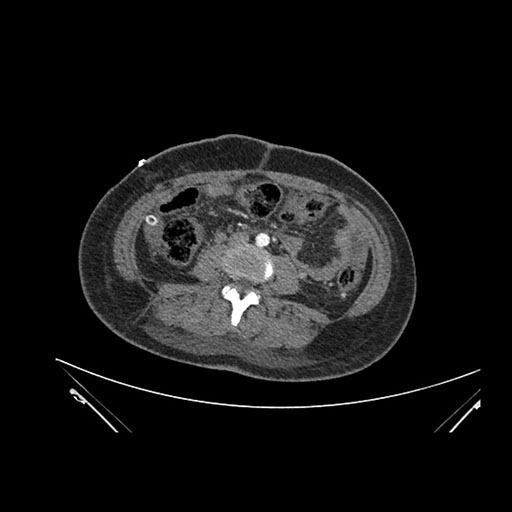

Axial Venous

Imaging analysis

Based on initial findings, which issue(s) would you be most concerned about?